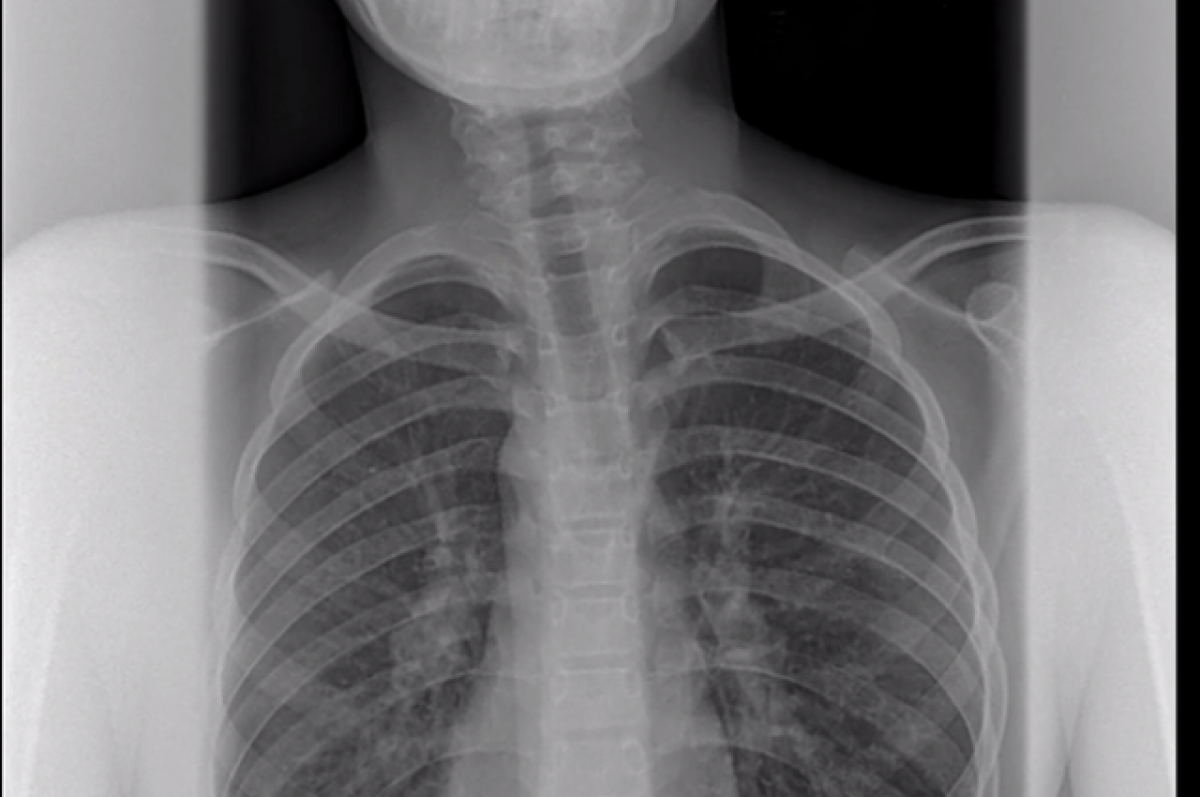

Врачи в Уфе спасли ребенка от инвалидности, исправив врожденную кривошею. Операцию провели врачи-ортопеды городской детской клинической больницы №17. Как сообщают в медучреждении, мальчику 11 лет. Врожденная патология доставляла ребенку массу неудобств и несла большую опасность, так как аномалия могла привести к ранней инвалидности. Пациенту провели операцию на грудино-ключично-сосцевидную мышцу. Операция прошла успешно, состояние ребенка улучшается.

Как сообщают в медучреждении, мальчику 11 лет. Врожденная патология доставляла ребенку массу неудобств и несла большую опасность, так как аномалия могла привести к ранней инвалидности. Пациенту провели операцию на грудино-ключично-сосцевидную мышцу. Операция прошла успешно, состояние ребенка улучшается.